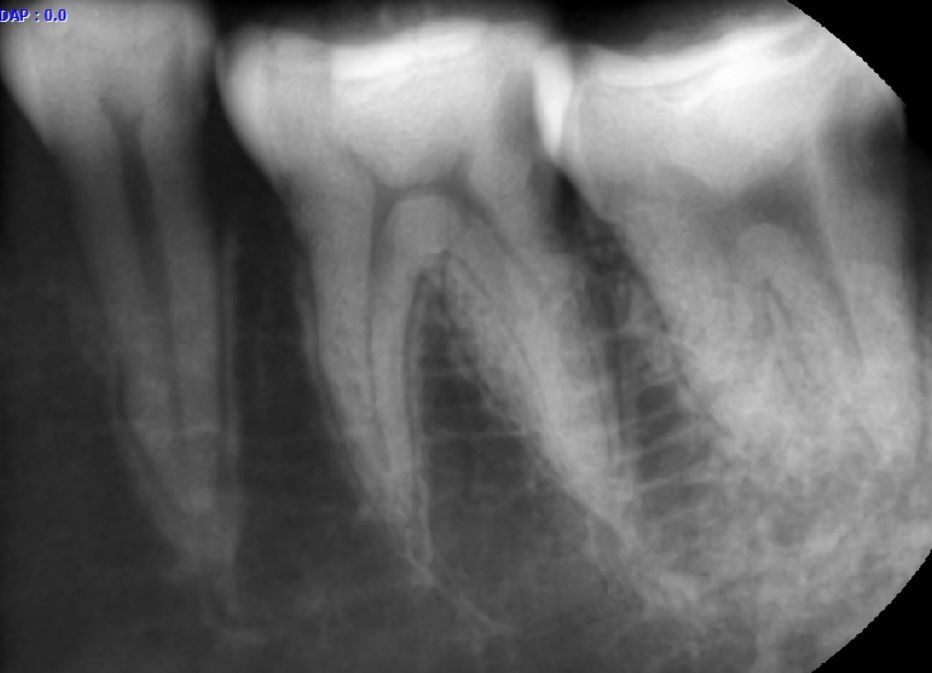

이 사진은 맨끝 어금니 빼고 신경치료 해야된다던 치아 입니다ㅜㅜ

• 2번 째 사진